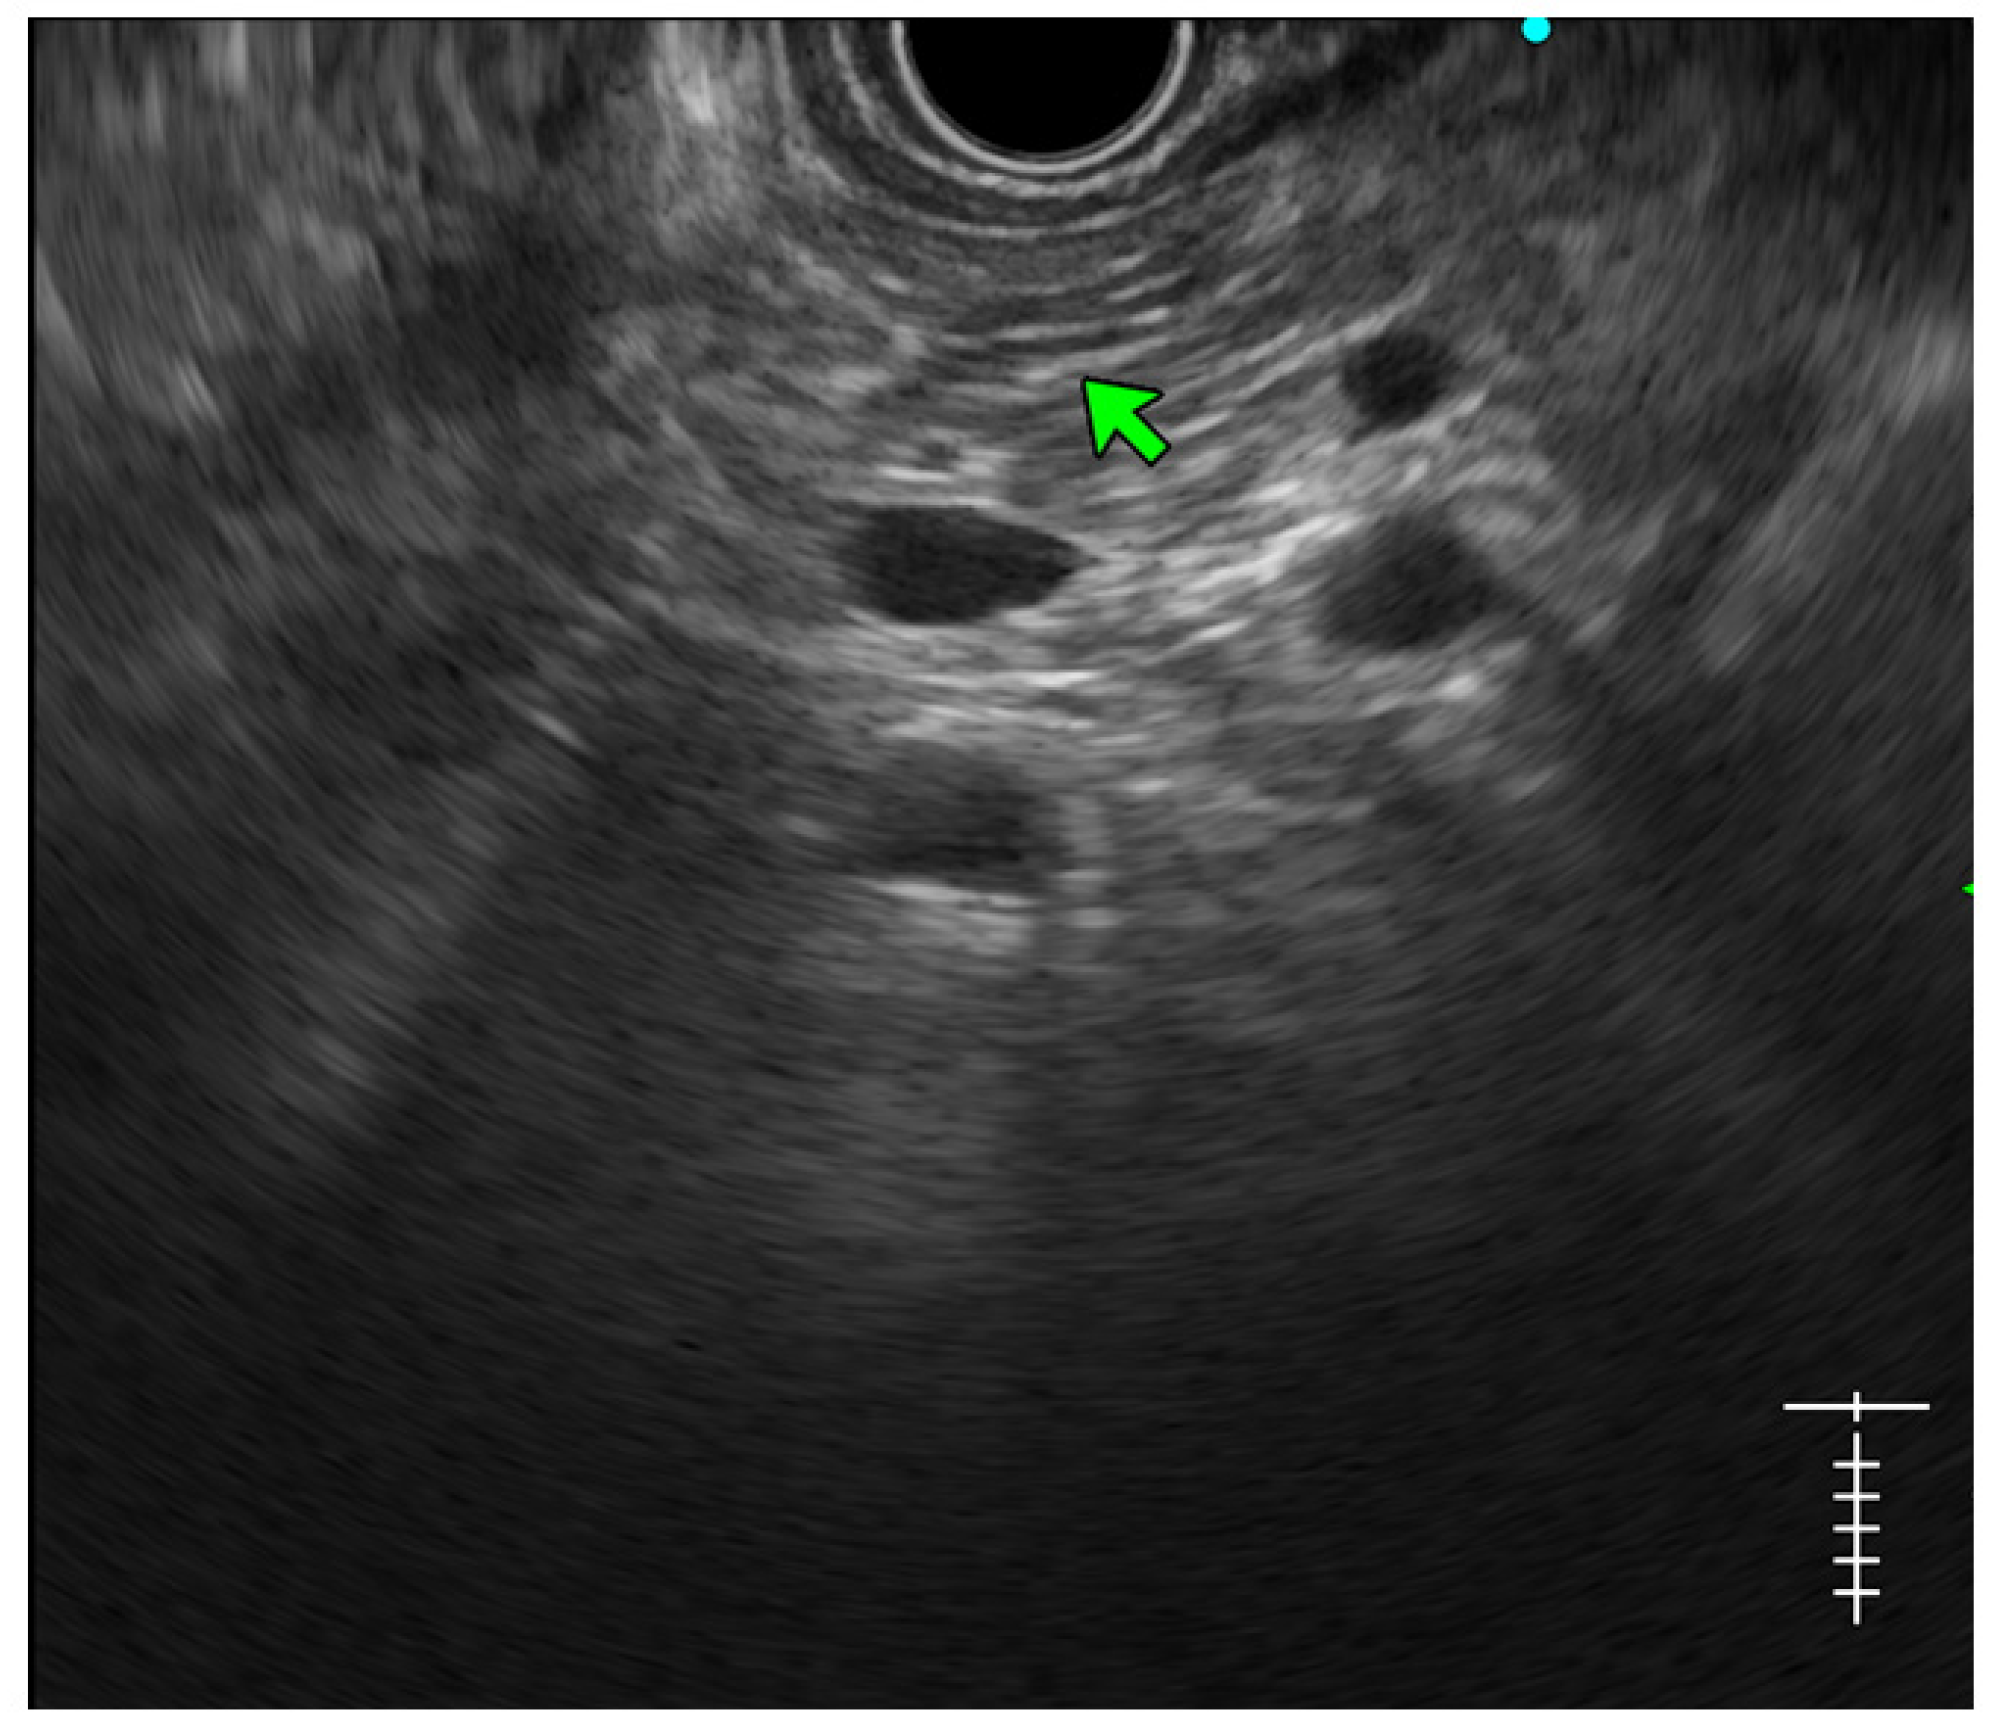

- Stranding: The presence of hyperechoic lines of ≥3 mm length in a minimum of two directions concerning the plane of imaging is described as ‘stranding’ in the JPS criteria (in standard criteria, it is described as hyperechoic foci with stranding). Abnormal stranding is described when at least three such lines are noted. Stranding corresponds to bridging parenchymal fibrosis in histopathology (Figure 4);